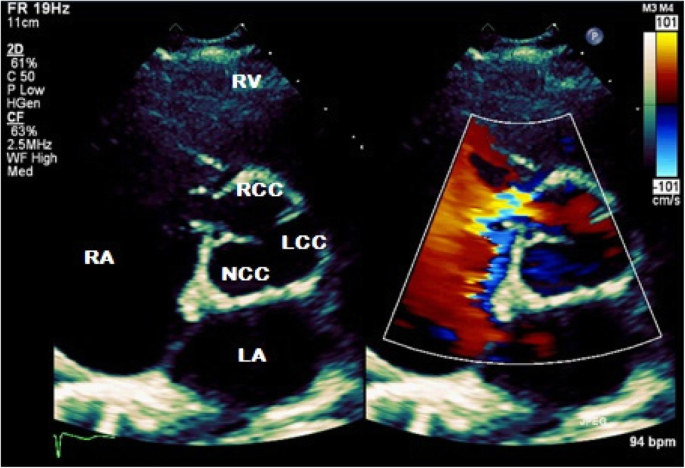

Transthoracic echocardiography (TTE) was subsequently performed for investigation of the new continuous murmur – other conditions apart from an SVA which can present with continuous murmurs include; patent ductus arteriosus, coarctation of the aorta, coronary arteriovenous fistulas and an aortopulmonary window. TTE showed normal left and right ventricular size and systolic function. To the unwary eye, the colour flow at the RV inflow view may appear like tricuspid regurgitation. However, the continuous wave Doppler clearly demonstrated a continuous wave form throughout systole and diastole (Fig. 1, Videos 1 and 2). Additionally, a significant left-to-right shunt was detected on the colour Doppler between the right coronary sinus and the right atrium (Fig. 2, Video 3). Interestingly, Doppler echocardiography detected diastolic flow reversal in the thoracic descending aorta which is more commonly seen in severe aortic regurgitation (Fig. 3).

Two-dimensional transthoracic echocardiography in parasternal short axis with colour compare view demonstrating a shunt from the right coronary sinus to the right atrium. RV, right ventricle; RA, right atrium; LA, left atrium; RCC, right coronary cusp; NCC, non-coronary cusp; LCC, left coronary cusp